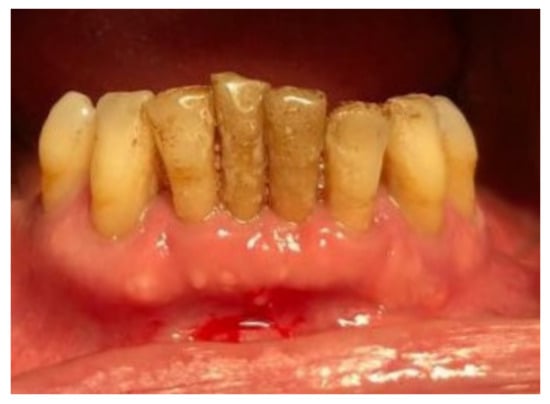

| Tissue colour: | 50% of gingiva red |

| Granulation tissue: | Present | |

| Incision margin: | Not epithelialized, with connective tissue exposed | |

| Suppuration: | None | |

| Granulation tissue: | None | |

| Incision margin: | No connective tissue exposed | |